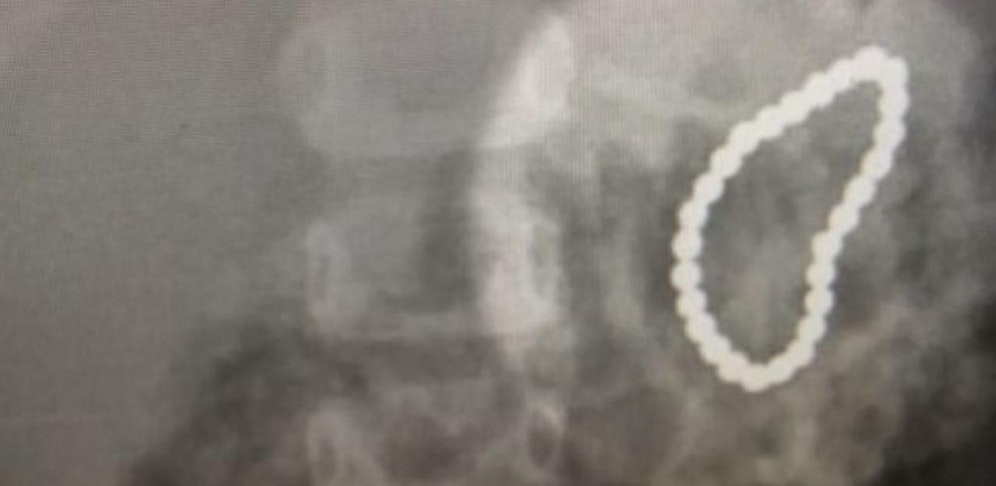

Im US-Bundesstaat Colorado wurde ein Kleinkind in die Notaufnahme eingeliefert. Das Mädchen hatte 28 kleine Magnetkugeln verschluckt.

Wie sich herausstellte, hatte das Mädchen die kleinen Magnetkugeln auf dem Schreibtisch seines Vaters entdeckt. Als dieser nach einem kurzen Besuch im Badezimmer wieder den Raum betrat, sah er seine Tochter mit einigen der Kugeln in der Hand. Aus Angst, sie könnte die Magnete verschluckt haben, entschied er sich, sofort ein Röntgenbild anfertigen zu lassen. Dieses bestätigte seine Vermutung. (red)